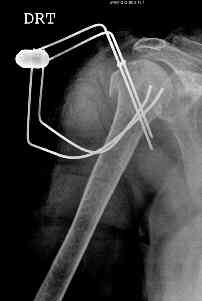

This fx need to be manipulated, reduced and fixed. We developed a minimally invasive ex fix with Ilizarov parts to fix it, we call it “Spider”, which can hold 4 fragments.

Attaching a case.